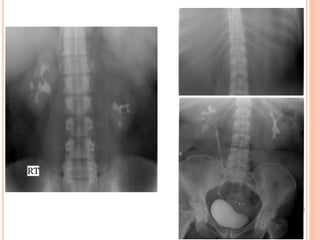

PLAIN RADIOGRAPHY(UTP)

- from the suprarenal

region to a level below

the symphysis pubis.

- The patient should void

immediately prior to

examination.

- may require additional

images

KUB

 Additional views:

- Oblique conventional

radiographs.

- Nephrotomogram.

- Open bladder film.

KUB ANALYSIS

 Musculoskeletal: evaluate all bone elements.

 Psoas muscle margin: straight, convex or absent.

 Intestinal gas: overlap, displaced.

 Kidneys

 Calcifications: overlying the UT or outside.

 Gas shadow: abnormal air at UT.

BLADDER

- Bladder contour.

- Wall thickness and

irregularities.

- Extrinsic compression.

- Filling defect.

- Post-void ( residual

urine, upper tract

dilatation).